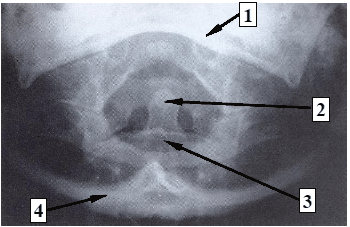

Assinale a alternativa que corresponde à sequência numérica (1, 2, 3 e 4) correta das estruturas especificadas na imagem.